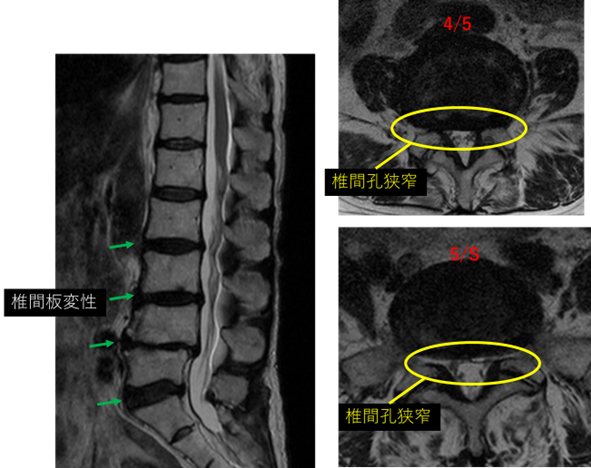

画像及び所見について

L1/2: 異常なし

L2/3: 変性

L3/4: 変性、膨隆

L4/5: 変性、膨隆、左椎間孔狭窄

L5/S: 変性、膨隆、両側椎間孔狭窄

以上の事が画像上認められます。

L3/4、4/5、5/S に

椎間板変性、椎間孔狭窄 を認め、主症状の原因の可能性が高い。